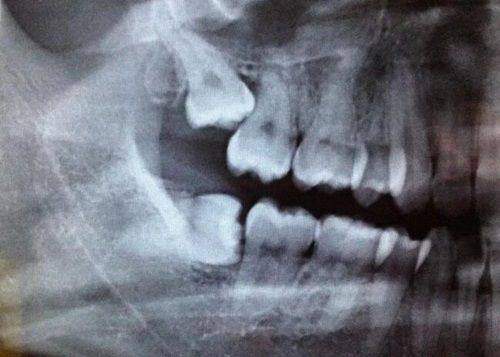

精良的设备是确保口腔治疗成效的重要因素。北京市回民医院口腔科引进了一系列国内外精良的口腔诊疗设备,如数字化口腔全景机、种植机、根管治疗仪等。这些设备能够为医生提供正确的诊断依据,提高治疗的精细度和安心性。例如,数字化口腔全景机可以清晰地显示牙齿和颌骨的结构,帮助医生更好地制定治疗方案;种植机可以严谨地植入种植体,提高种植牙的成功几率。